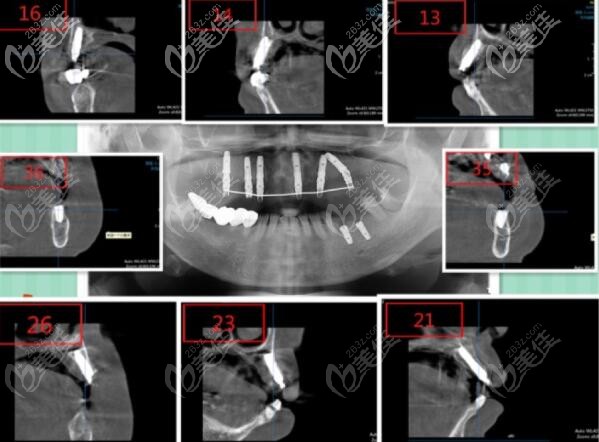

今天就来分享一份三亚鼎点口腔做的韩国登腾Dentium上颌all-on-6即刻负重种植牙案例,看看这位63岁的高龄老人,做完活动假牙后为什么又选择了种植牙呢?

三亚鼎点口腔做的all-on-6半口即刻负重种植牙真实案例:

症状:口腔检查上半口只剩下两个残冠。

医生设计的方案是:上颌韩国登腾做ALL-ON-6即刻负重,6个月后进行全瓷冠固定修复。

用的韩国登腾种植体,因为登腾种植牙对于牙槽骨吸收病例在临床上也有很高的成功率,而且性价比高,顾客也可接受。

看做完半口种植牙的效果图:

并且你看顾客做的韩国登腾半口种植牙有没有和真牙很像?